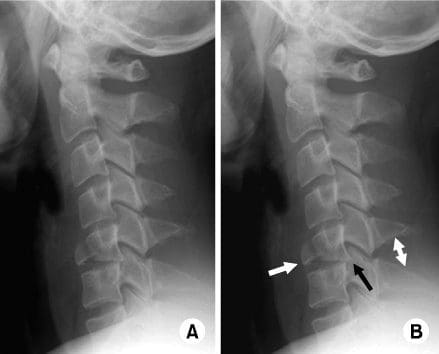

A teardrop fracture is caused when the anteroinferior aspect of a cervical vertebral body is damaged due to flexion of the spine together with vertical compression. The fracture throughout the body is also associated with deformity of the human body and subluxation or dislocation of the facet joints. A teardrop fracture is generally associated with a spinal cord injury due to the displacement of the anterior portion of the body into the spine.

The flexion teardrop fracture shouldn’t be confused with a similar-looking vertebral fracture called “expansion teardrop fracture”. Both usually happen in the cervical spine, but as their names indicate, they result from other mechanisms (flexion-compression vs. hyperextension). Both are linked to a small fragment being broken apart from the anteroinferior corner of the affected vertebra. Flexion teardrop fractures normally involve instability in most elements of the backbone, commonly occur at the C4-C7 vertebra, and have a higher association with spinal cord injury (specifically anterior cord syndrome). In contrast, the extension-type fracture happens more commonly in C2 or C3, causes significantly less if any disturbance to the middle and posterior elements, and does not normally result in spinal cord injury (but it may co-occur with more harmful spinal injuries).

A flexion teardrop fracture is a common injury of the cervical spine, or neck, which can be severe in nature. Its name is characterized by the triangle-shaped fragment which typically fractures from the anteroinferior corner of the vertebral body and that resembles a drop of water dripping from the vertebral body. The scope of our information is limited to chiropractic, spinal injuries, and conditions. To discuss the subject matter, please feel free to ask Dr. Jimenez or contact us at 915-850-0900 .